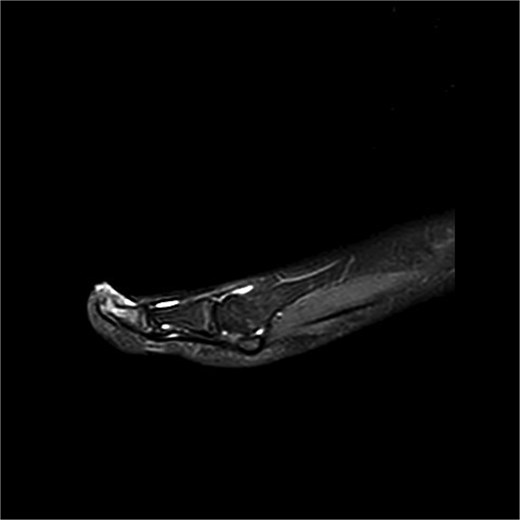

Case 3

Preoperative MRI from case 3 demonstrating SE and associated bone marrow edema.